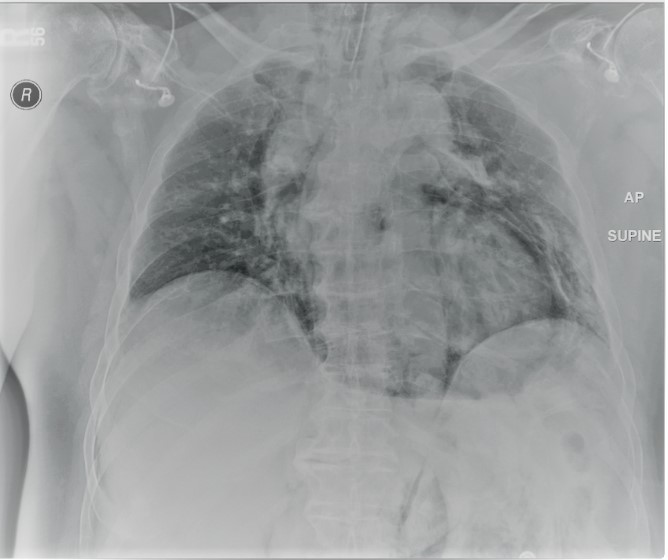

A 72-year-old gentleman with achalasia who weighed 91 kg was admitted for an elective POEM procedure (Figure 1). The procedure started with stable hemodynamics on a constant ventilator setting of respiratory rate of 10-16/hr; tidal volume of 443; positive end-expiratory pressure (PEEP) of 5 cm H2O; positive inspiratory pressure of 22-24; end tidal carbon dioxide of 28; arterial oxygen saturation of 100. However, 45 minutes into the procedure, the patient went into pulseless electrical arrest. The scope was withdrawn, and he was revived after 10 minutes of cardiopulmonary resuscitation. The procedure was aborted and he was transferred to the ICU intubated, critically ill, and on escalating doses of epinephrine and norepinephrine. Follow-up diagnostic imaging (Figures 2 and 3) showed a small heart with air tracking around it, the mediastinum, the esophagus, and the aorta, confirming tension pneumomediastinum.

Under echo-guided pericardiocentesis, the cardiogenic shock was instantaneously reversed upon entry of the needle into the highly pressurized pericardial sac. A total of 600 cc of air and very minimal serosanguinous fluid was evacuated through a 3-way stopcock with a 50 cc syringe. The patient's inotropic support and pericardial drain were discontinued within 36 hrs. Under endoscopic guidance, botox injections were performed 4 days after his cardiac arrest. He was ultimately extubated on postoperative day 8, after being treated for aspiration pneumonia. Follow up esophagram done a month later showed findings compatible with achalasia with no evidence of a leak. The patient was discharged after 54 days due to complications of aspiration pneumonia, sepsis, and acute kidney injury. During a 6-month follow-up visit, the patient's esophagogram showed achalasia, but he reported relief of symptoms of achalasia.